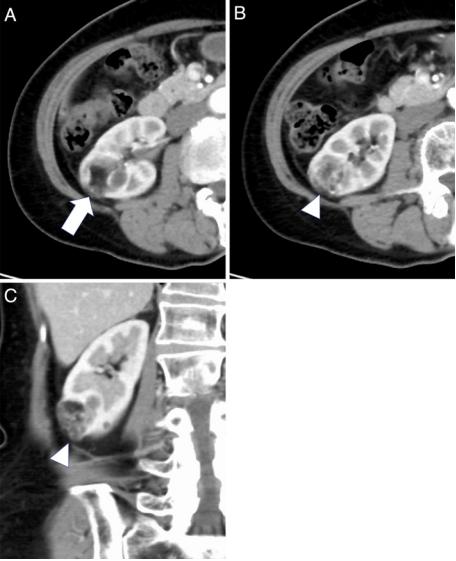

患者女性,70余岁。2年前被诊断为无症状,散发性,典型AML。既往有高血压病史,正在服用钙离子通道阻滞剂。对比增强CT (CECT)显示右肾后下段有一个18×21×25mm的混合密度肿块,其中包括脂肪和血管成分。尽管未发现瘤内动脉瘤>5mm,但丰富的血管病变向肾后周间隙突出(图1)。

图1、肾血管平滑肌脂肪瘤破裂的患者2年前对比增强计算机断层扫描(CECT)。CECT显示右肾后下段一个18×21×25 mm的混合密度肿块,包括脂肪(A,箭头)和丰富的血管成分(1B和1C,箭头)。CECT显示高血管病变突出至肾周间隙,但未见瘤内大于5mm的动脉瘤(1B和1 c,箭头)